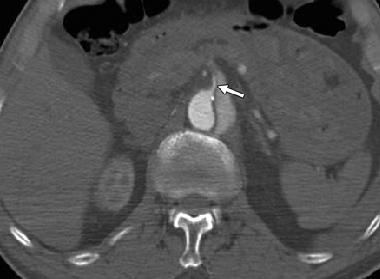

Hình 15: Vành bóc tách gần nguyên ủy động mạch mạc treo tràng trên. Trên hình axial, vành bóc tách chạy qua nguyên ủy động mạch mạc treo tràng trên. Nếu lòng giả lớn thêm, vành bóc tách có thể sa xuống dần qua nguyên ủy động mạch gây tắc động của động mạch này.

Hình 16: Biến chứng của bóc tách động mạch chủ ngực. Hình axial ngang qua bụng cho thấy vành bóc tách liên quan nguyên ủy động mạch mạc treo tràng trên (mũi tên). Thấy vành bóc tách đi vào nguyên ủy động mạch, vì vậy gây tổn thương lòng mạch. Kiểu tắc này được điều trị bằng đạt stent nội mạch.